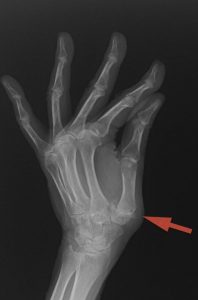

La rizartrosis es la artrosis de la articulación de la base del pulgar.  (Figura 1)

PATOLOGÍAS EN MANO Y DEDOS - RIZARTROSIS Figura 1 - Radiografía de una Rizartrosis

Figura 1 - Radiografía de una Rizartrosis

Los síntomas de la Rizartrosis incluyen el dolor en la base del pulgar al agarrar objetos o al realizar movimientos de pinza.  Muy frecuentemente el dolor se produce al abrir botes, agarrar y girar el pomo de la puerta o al girar una llave.  La fuerza de agarre y la pinza disminuye a medida que la Rizartrosis empeora y en los casos severos o avanzados la base del pulgar suele deformarse debido a la dislocación parcial o subluxación de la articulación debido al desgaste de la misma (Figura 2).

El diagnóstico de la Rizartrosis se hace mediante a exploración física y ante los hallazgos de dolor e inflamación previamente comentados.  Durante la exploración se puede llegar a notar el roce entre los huesos al mover el pulgar.  Las Radiografías demuestran los signos clásicos de la artrosis: disminución del espacio articular, formación de osteofítos (o espículas óseas) alrededor de la articulación e incluso la subluxación de la articulación (dislocación) en casos avanzados.